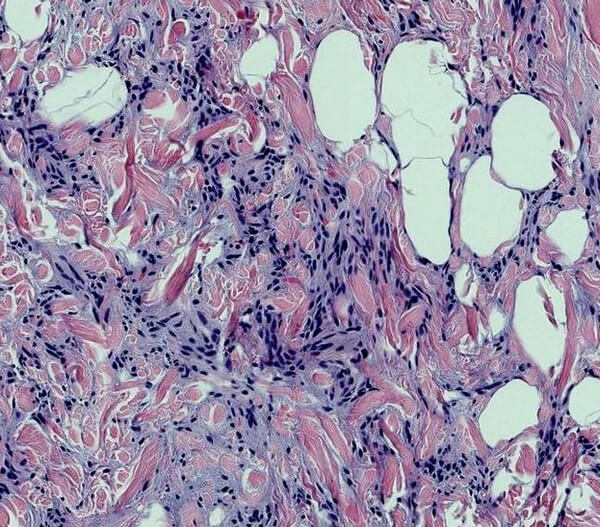

lipofibromatous tumors – Humpath.com – Human pathology

Atypical Lipomatous Tumor/Well-Differentiated Liposarcoma …